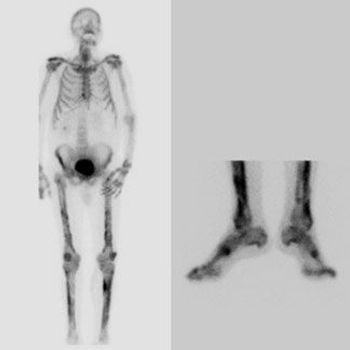

She presented with such severe calf pain she could no longer walk unassisted, with a months-long history of fever of unknown origin. What does the MRI show?

This young woman presented with severe leg pain, night sweats, and fever of unknown origin. The diagnosis of polyarteritis nodosa had several unusual features.